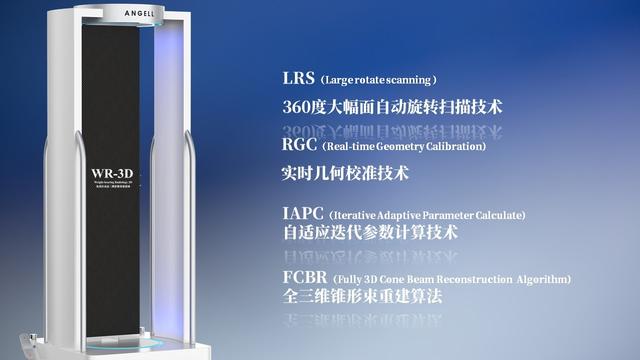

安健科技基于數字化X線攝影技術創新的WR-3D負重位多角度三維掃描系統

安健科技WR-3D負重位動態三維攝影技術